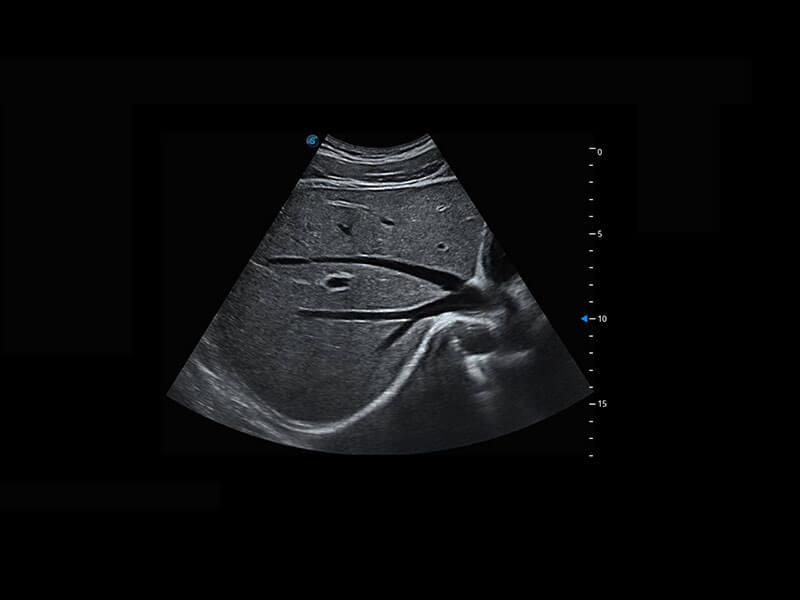

P60在胎儿早孕期超声筛查中为您带来优异的图像质量。

早孕-胎心

高分辨率容积成像-早孕胎儿

胎儿体循环

光影成像-孕囊